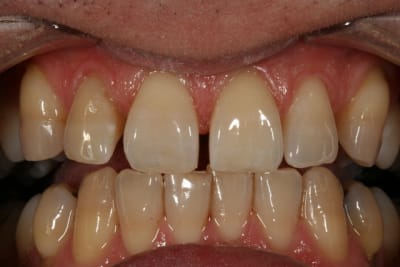

Un cas de blanchiment interne .

Cas simple et pourtant ... j'ai été obligé de prendre un risque . Lequel ?

C'est un blanchiment unitaire sur dent vivante ayant eu traumatisme.

C'est un blanchiment interne comme si l'endo était faite (après recherche effrénée d'un hypothétique canal), et après contrôle +++ d'une isolation +++ . La patiente n'a aucun souvenir d'un traumatisme sur cette dent .

Le protocole est le même que pour une dent dépulpée ; isolation en regard présumé du canal , un peu plus parce que j'ai cherché un moment en plusieurs séances . Perborate , et voilà .

3 séances à 7 jours d'intervalles .

Si on décide d'être le moins invasif , j'ai jugé raisonnable de tenter quand même malgré l'impossibilité de repérage de l'entrée du canal . Faire une facette c'est passer un cap , et je n'ai de prothésiste capable de reproduire les stries visibles sur la photo de départ de tout façon donc je n'ai compté que sur moi même .